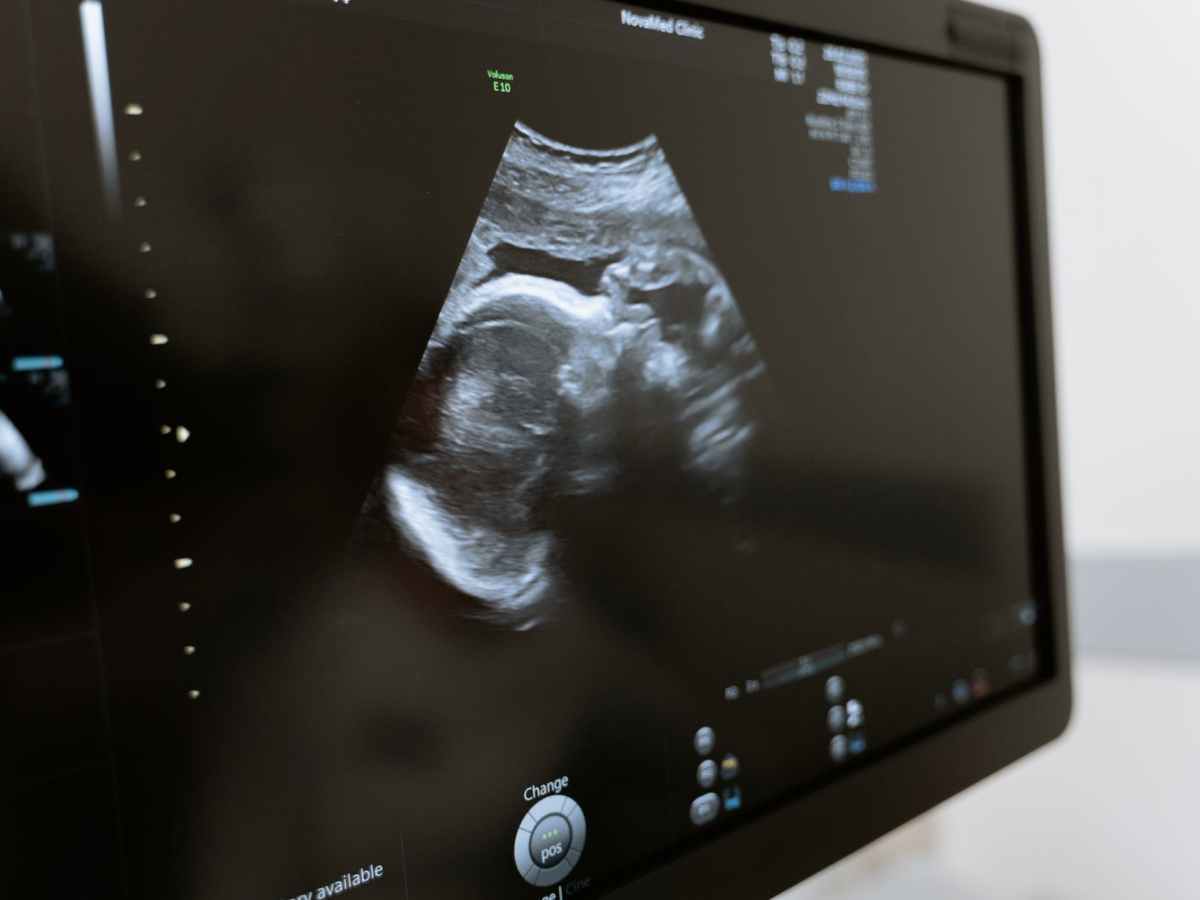

Midden in de nacht staat er een vrouw met haar partner bij de balie op de verloskamers. Ze is zo’n vijf maanden zwanger en ze heeft heel erg buikpijn. Ze wordt op een verloskamer gelegd en al snel blijkt dat ze gaat bevallen, maar is ze al 24 weken zwanger? Gaan we het kindje behandelen…

Keep reading